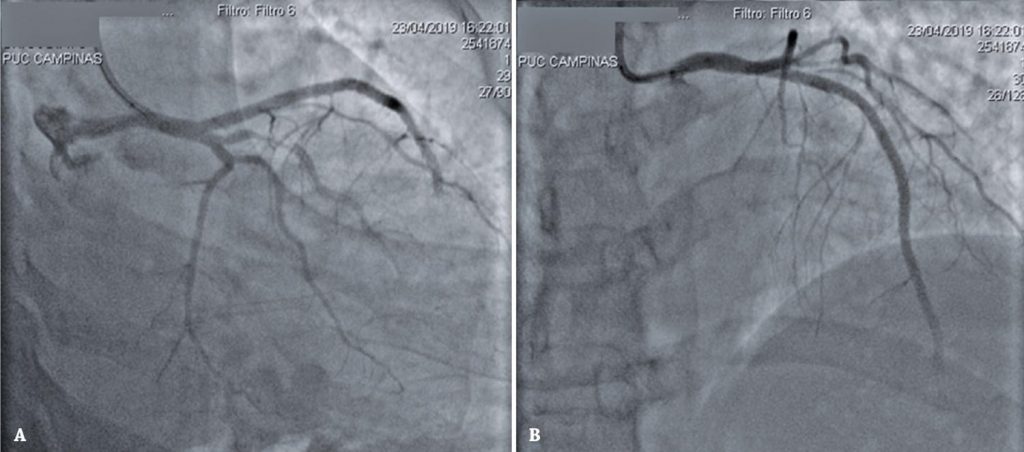

Figura 4

Cinecoronariografia evidenciando resultado do procedimento. (A) Projeção oblíqua anterior direita caudal mostra dissecção de ramo marginal, mantida em tratamento conservador. (B) Em projeção oblíqua anterior direita cranial, observam-se três stents em artéria descendente anterior, sem opacificação do leito distal dessa coronária.